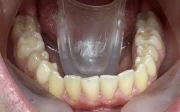

Стрипинг

Serviciul a fost efectuat la Дентално студио ТОП ДЕНТАЛ de томи пелова pe 9 Okt., 25